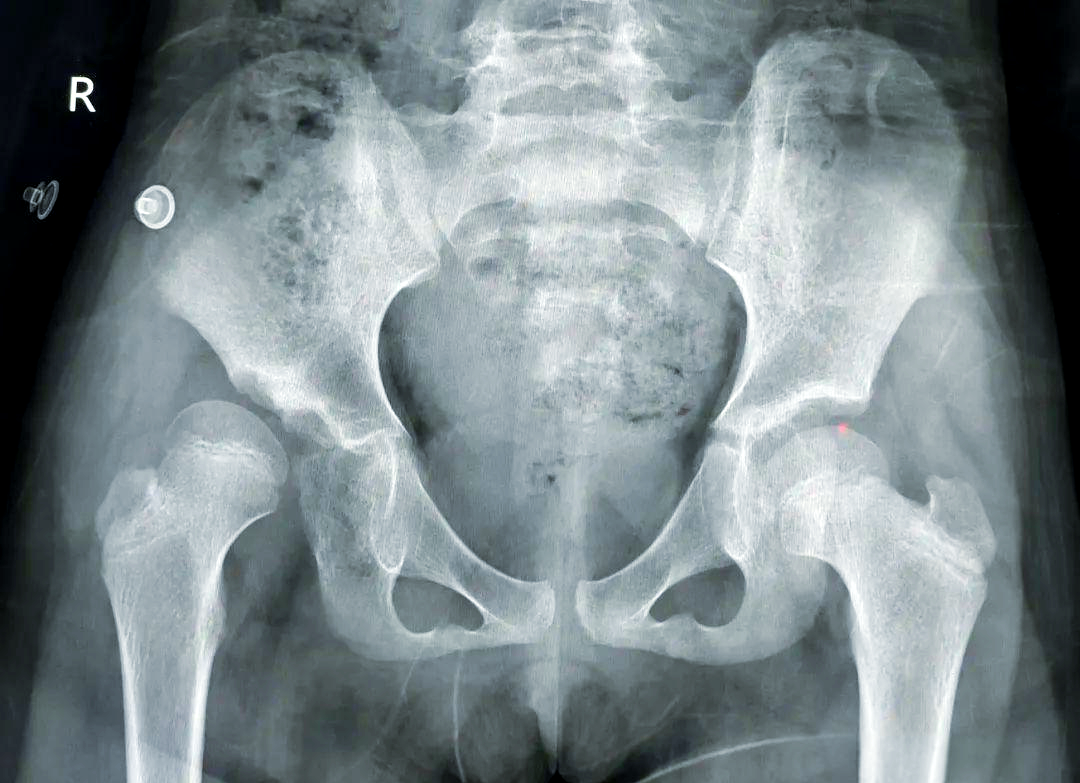

会诊手术! 马蹄内翻足 发育性髋关节脱位 学科带头人介绍 卢成 骨科主任 从事骨科临床工作二十多年,曾于2011年在清华大学附属医院师从中国著名矫形外科专家秦泗河教授学习矫形外科,积累了大量的临床诊疗经验。熟悉骨科常见病、多发病的诊断及治疗,在四肢畸形矫正及骨外固定技术领域有较深的造诣。 擅长:骨外固定及Iizarov技术治疗各种下肢畸形包括脊髓灰质炎后遗症、脑瘫肢体功能障碍、先天性髋关节脱位、膝内、外翻、先天性多发性关节挛缩症、骨缺损、骨不连、骨髓炎,以及先天性马蹄内翻足、拇外翻等各种复杂的足踝部畸形、脊柱裂后遗各种下肢畸形等。同时在成骨性肿瘤、成软骨性肿瘤、骨肉瘤等骨肿瘤疾病的治疗,股骨头坏死、颈椎病/腰椎病的手术治疗、椎体成形术、关节创伤、关节置换等方面也有颇深的造诣。 欢迎安徽省及周边地区患友积极就诊、复查。凡在